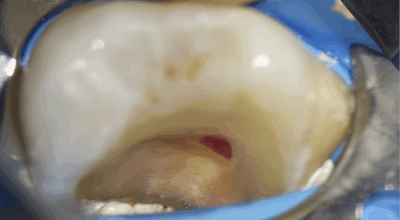

Pulpotomie partielle

Parfois il y a besoin d’aller volontairement un peu plus loin dans la pulpe. C’est le cas lorsque l’hémostase n’est pas obtenue, ou bien lorsqu’il y a la nécessité de réaliser un minimum de coffrage pour maintenir le biomatériau bioactif.

Cas clinique

Pulpotomie partielle : 88,2% de taux de succès